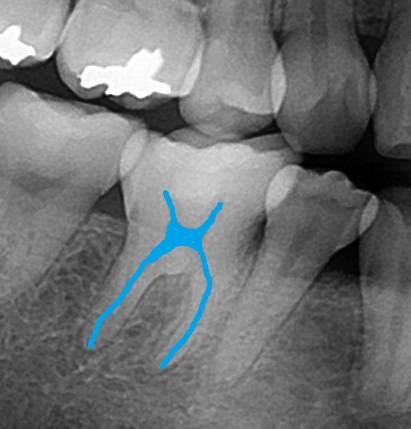

エックス線写真で確認してみると、

このような状態で歯の中が見えます。

レジンは少し白目で写りますので、

ここに詰まっています。

歯の神経は黒く見えますので、

ここに神経が写っています。

照らし合わせてみると、

神経近くの深いところまでレジンが詰めてあるのが確認できます。